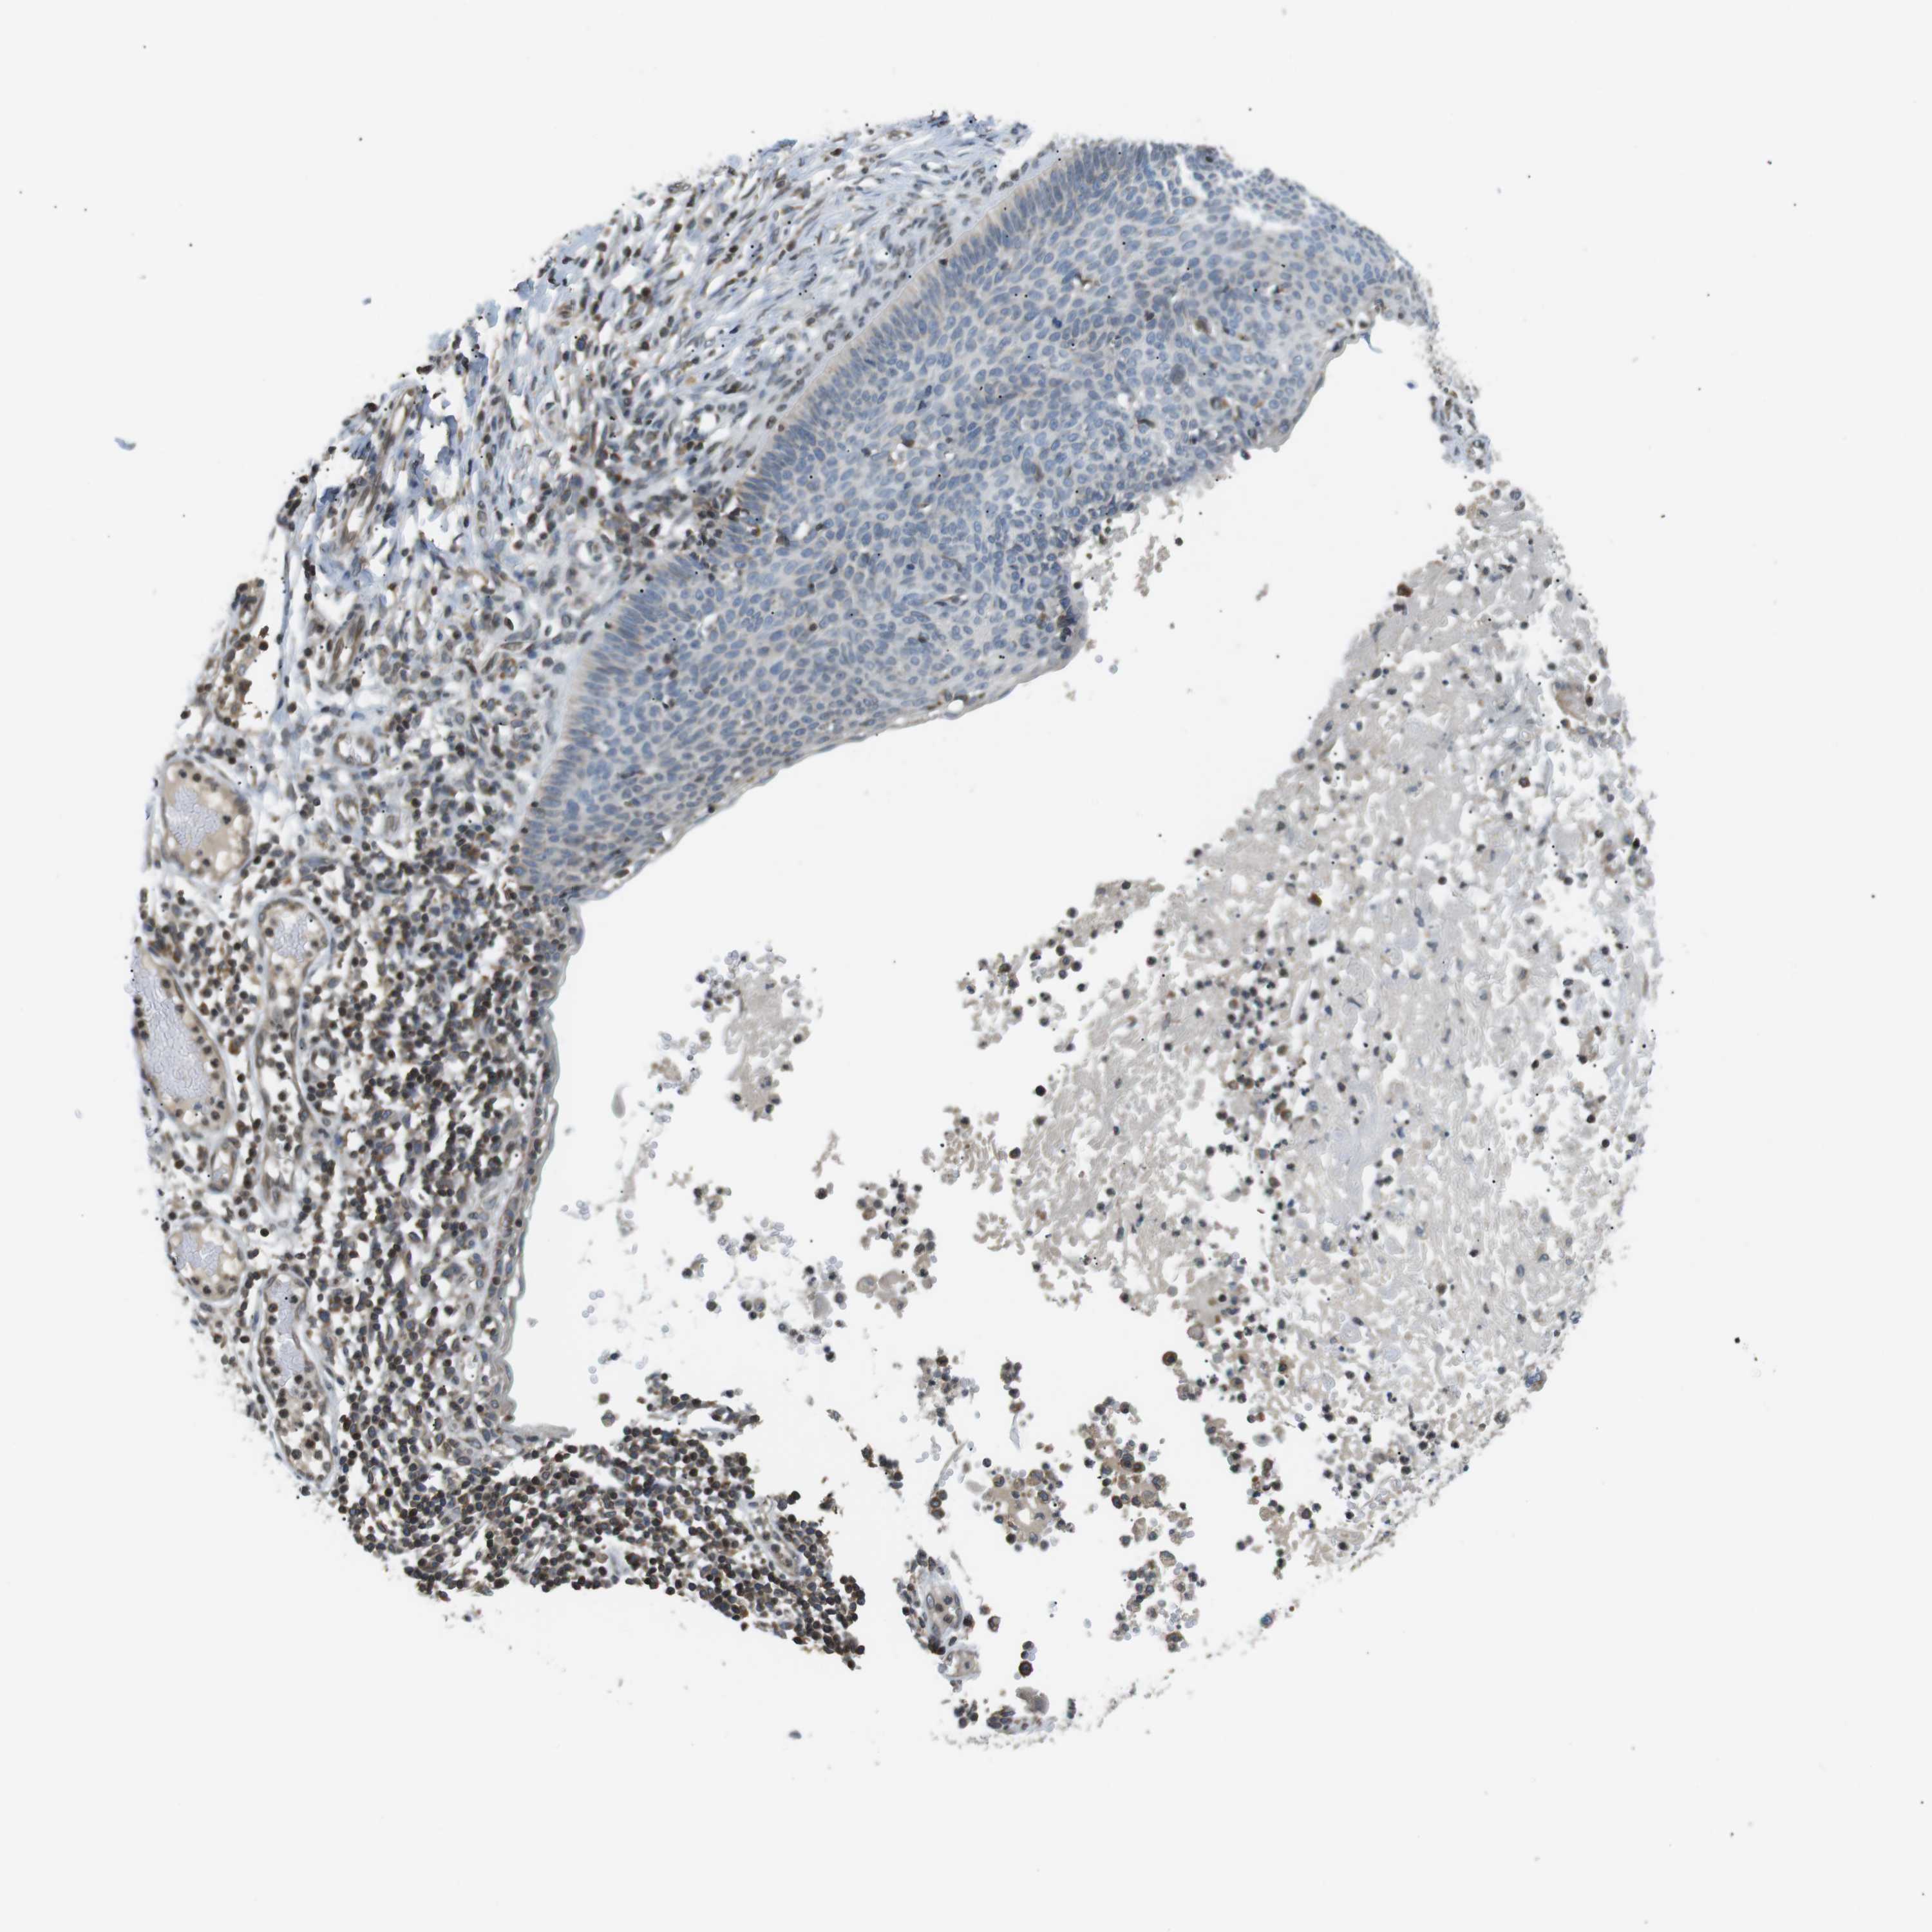

SKIN CANCER - Protein expressioni

A mouse-over function shows sample information and annotation data. Click on an image to view it in a full screen mode. Samples can be filtered based on level of antibody staining by selecting one or several of the following categories: high, medium, low and not detected. The assay and annotation is described here.

Antibody stainingi

Antibody staining in the annotated cell types in the current human tissue is reported as not detected, low, medium, or high, based on conventional immunohistochemistry profiling in selected tissues. This score is based on the combination of the staining intensity and fraction of stained cells.

Each image is clickable and will lead to virtual microscopy that enables deeper exploration of all samples and also displays staining intensity scores, fraction scores and subcellular localization as well as patient and tissue information for each sample.

Antibody HPA015752

Squamous cell carcinoma, NOS